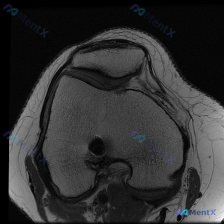

本次读片对象是单张膝关节矢状位T1加权MRI影像,临床提示需要排查是否存在可视化软骨异常。

- 骨性结构:股骨远端、胫骨近端骨髓信号正常(脂肪髓高信号),骨皮质连续,没有骨质破坏、骨折或者明显骨赘

- 软组织结构:半月板形态完整,信号均匀低信号,没有明确内部高信号;前后交叉韧带、伸膝装置(股四头肌腱、髌腱)连续性良好,信号正常

- 关节软骨:股骨髁关节面软骨厚度均匀,软骨下骨皮质光滑,没有看到明确的局灶变薄、剥脱改变

- 关节腔与软组织:没有明显关节积液,腘窝软组织也没有占位或肿胀